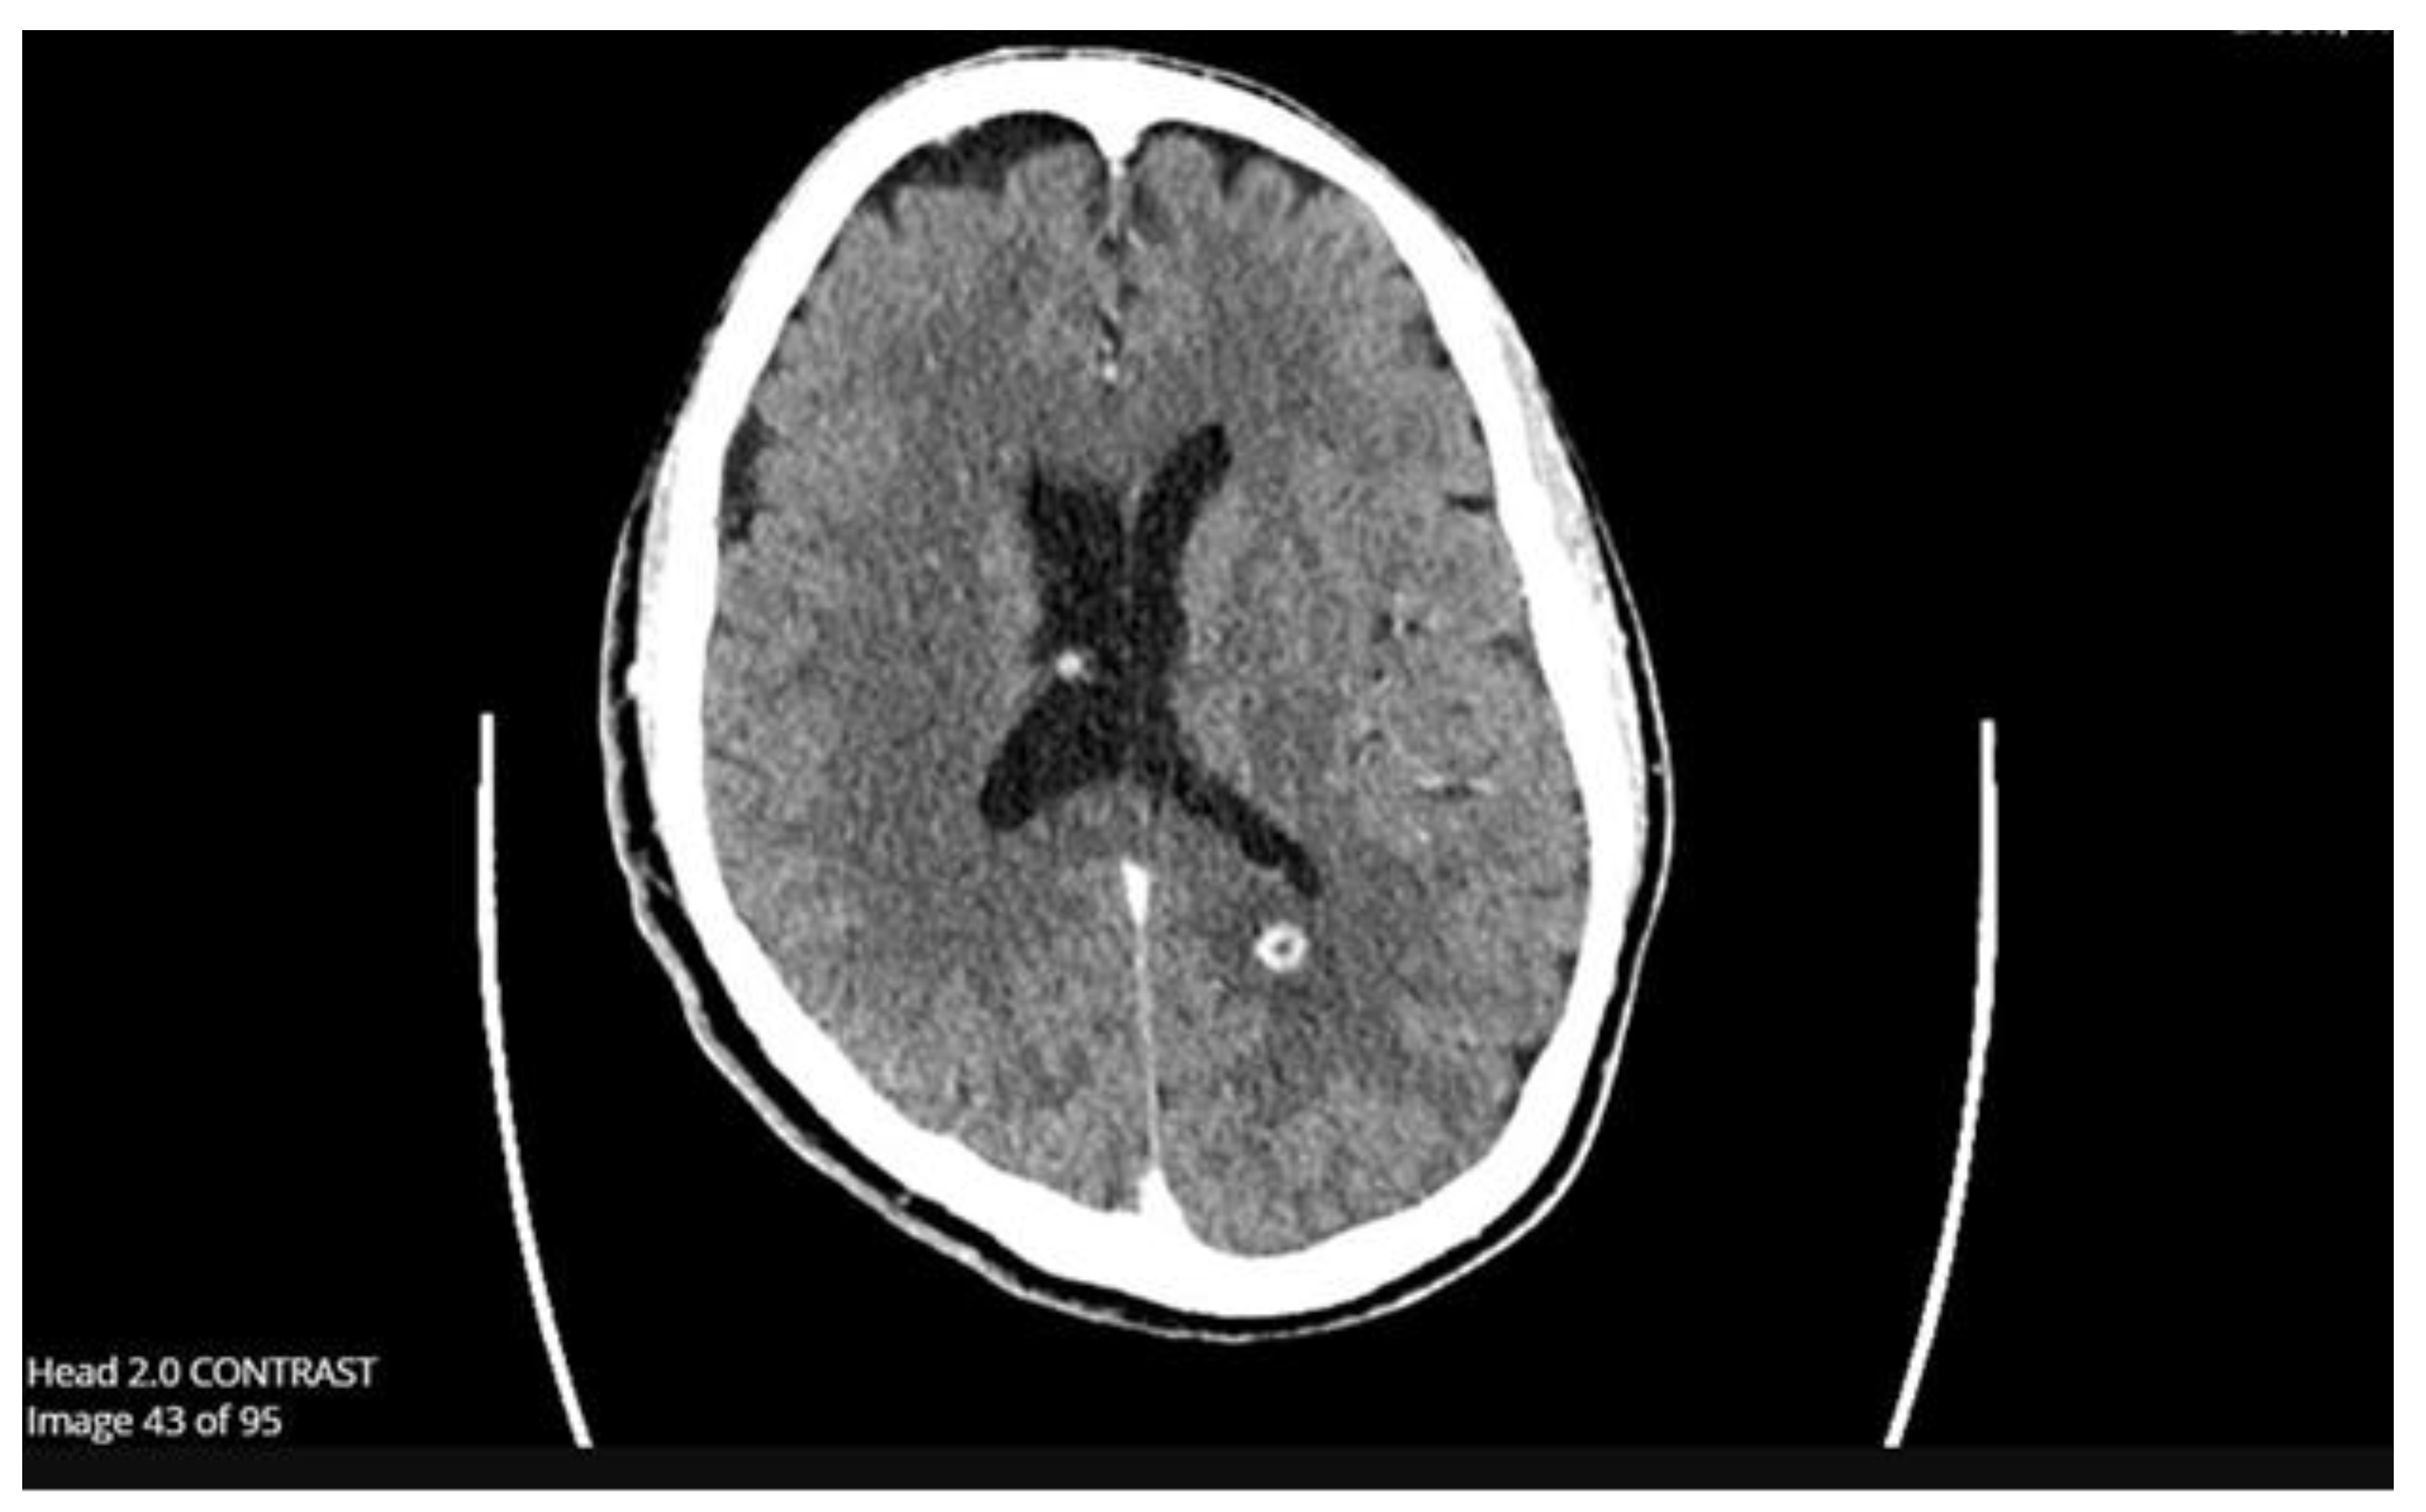

While inpatient at his initial hospitalization, the patient was found to have right upper lobe pneumonia and was treated with cefepime and vancomycin. Initial infectious workup with blood cultures, respiratory cultures, and viral respiratory panel was unremarkable. An MRI with contrast of the lumbar spine was obtained to evaluate his acute back pain, which demonstrated soft tissue edema and myositis with a possible abscess and subtle osteomyelitis of the L3-L4 facet joint and transverse process. Given these findings, the patient underwent a CT-guided aspiration of the paraspinal abscess by interventional radiology, with cultures yielding Nocardia transvalensis. The patient was transitioned to trimethoprim-sulfamethoxazole, ceftriaxone, and linezolid, but left against medical advice shortly afterward.

Upon re-admission for persistent symptoms in his second hospitalization, the patient’s vitals were: blood pressure of 170/92 mmHg, heart rate of 79 beats/min, and temperature of 36.7 °C. Lab workup was notable for a lactic acid of 1.7 mmol/L (normal: 0.4 – 2.0 mmol/L), white blood cell count of 6.0 x 10E9/L (normal: 4.0 - 11 x 10E9/L), a procalcitonin of 0.10 ng/mL (normal: < 0.05 ng/mL), a CT head revealed 9 mm enhancing supratentorial lesions (Image 1: Supratentorial Lesions on CT Head), and a repeat MRI of the lumbar spine demonstrated concerns for a neoplastic process from the spinous process of L2 (Image 2: Concerns of Neoplastic Processes on Spinal MRI). The reviewing radiologist favored lymphoma with additional involvement of the bilateral inferior articular process. Neurosurgery consultation deemed no significant interventions for his cranial lesions necessary. However, the patient underwent an IR-guided biopsy of the spinal lesion, ultimately yielding only granulation tissue without evidence of malignancy. Given his housing instability, the patient’s final antibiotic regimen based on susceptibility and feasibility entailed oral levofloxacin, oral linezolid, and oral trimethoprim-sulfamethoxazole (Table 1: Susceptibility Pattern of Nocardia Transvalensis).

Figure 2. Concerns of Neoplastic Processes on Spinal MRI.

The management in this case likewise matched the pace at which diagnostic information was available to us. Initially, broad-spectrum antibiotics with vancomycin and cefepime were appropriately given for a presumed pneumonia. While his pulmonary workup was relatively unfruitful, what clued us in to the diagnosis was the patient’s history of complaining of incidental back pain. While musculoskeletal pain is a common complaint in inpatient and outpatient settings, this patient attained dedicated and proper attention to his subacute lumbar back pain through formal imaging. It was by detecting subtle osteomyelitis of the L3-L4 facet joint and transverse process with a concerning paraspinal abscess that a biopsy was able to be performed. When the patient left his first hospitalization against medical advice, antibiotic susceptibilities were not available at the time. The empiric regimen was transitioned to trimethoprim-sulfamethoxazole, ceftriaxone, and linezolid in response to the new detection of Nocardia transvalensis, which was very appropriate given the susceptibility data in the limited literature, need for a regimen with high penetrance to central nervous system tissue, and the final susceptibilities of this strain [9,19,20].